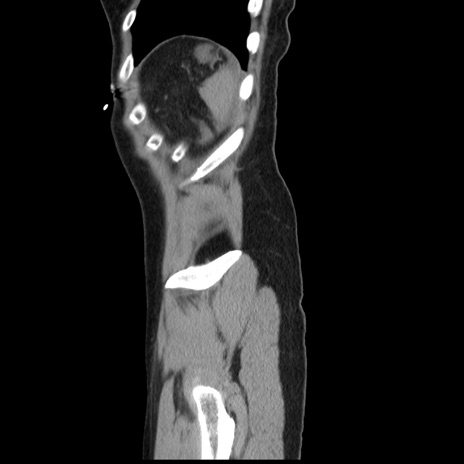

症例10(矢状断像)

【症例】 50歳代女性

【主訴】 腹痛

【現病歴】前日生レバーを食べた。今朝に排便あり。 昼前に突然発症の腹痛を生じ、当院救急外来を受診した。

【既往歴】 子宮筋腫にてで子宮全摘後

【身体所見】 意識清明、腹部:平坦、軟、下腹部やや左を中心に圧痛・反跳痛あり、筋性防御あり

【データ】WBC 7800、CRP 0.07